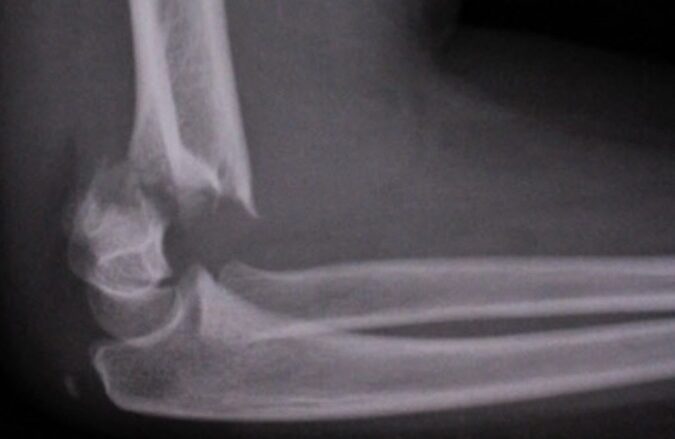

肘の骨折の回復期間は、さまざまな要因によって異なることがありますが、一般的には3ヶ月から6ヶ月程度とされています。この期間は、骨折の種類や重症度、個人の健康状態により変動します。私たちは、この回復プロセスを理解し、その過程で何を期待できるかを知ることが重要です。

手術が必要な場合の全治期間について

手術が必要な肘の骨折の場合、全治期間は一般的に長くなる傾向があります。手術を受ける理由としては、骨片がずれている場合や、複雑な骨折が発生した時などが挙げられます。このようなケースでは、手術後の回復過程も慎重に行う必要があります。

手術後の全治期間に影響を与える要因には以下のようなものがあります:

- 骨折の種類: 単純骨折と複雑骨折では、回復にかかる時間が異なります。特に複雑な場合は、再建や固定が必要であり、その分リハビリテーションにも時間がかかります。

以下は一般的な全治期間の目安です:

| 状況 | 全治期間 |

|---|---|

| 単純骨折(手術なし) | 約3〜6ヶ月 |

| 複雑骨折(手術あり) | 約6〜12ヶ月 |

| 高齢者・慢性疾患患者(手術あり) | 約12ヶ月以上 |